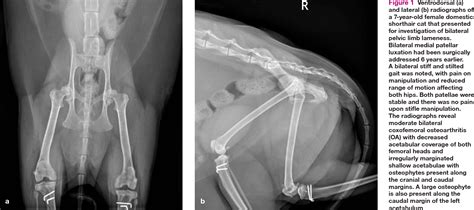

Rita Eustice Blog